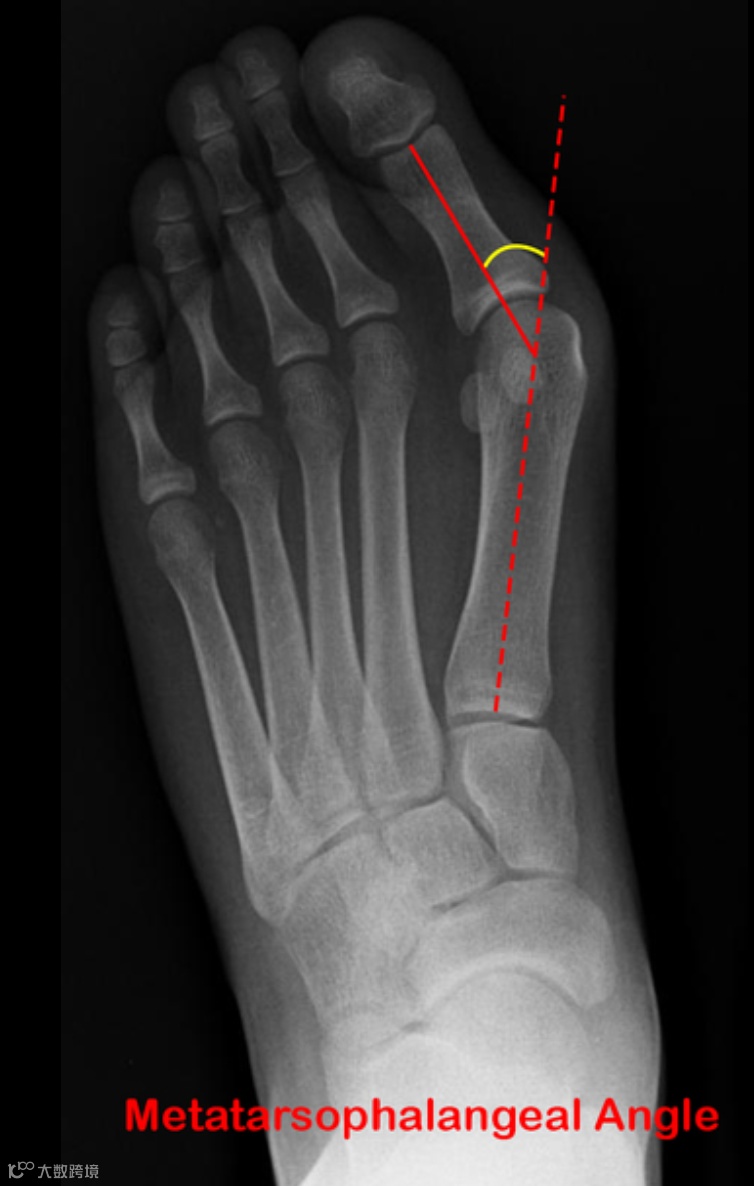

拇外翻角(HVA)

也称第一跖趾角,第一跖骨和近节趾骨干中线之间的夹角

正常值小于15°

诊断标准:HVA ≥ 15°

若HVA≥15°,可诊断为拇外翻。